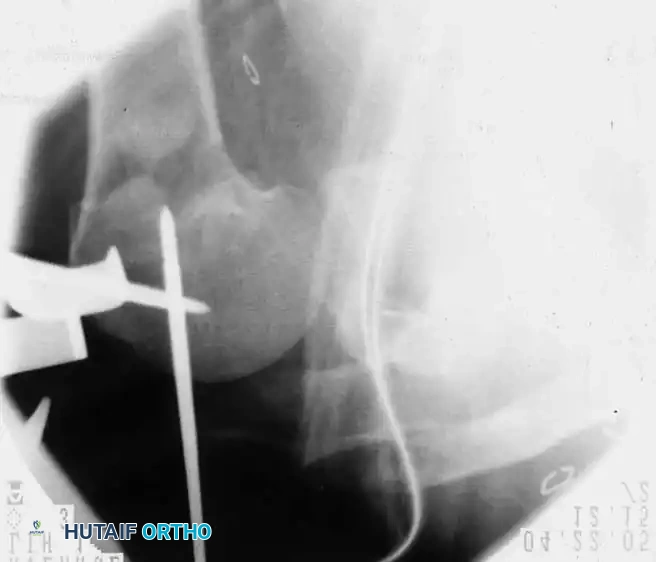

Percutaneous Pinning

Percutaneous pinning offers the distinct advantage of avoiding extensive soft-tissue dissection, thereby maximally preserving the blood supply to the humeral head. It is a minimally invasive, cost-effective technique. Jaberg et al. and Resch et al. have reported excellent outcomes using threaded pins or Kirschner wires.

Technique Overview:

* Closed reduction is achieved under fluoroscopy using traction, abduction, and manipulation.

* Pins are introduced percutaneously from the lateral humeral cortex, directed superomedially into the humeral head.

* Additional pins may be placed anteriorly to secure the lesser tuberosity or superiorly for the greater tuberosity.

* Warning: The axillary nerve is at risk during lateral pin insertion. Pins must be placed carefully, often utilizing a small stab incision and blunt dissection to the bone.